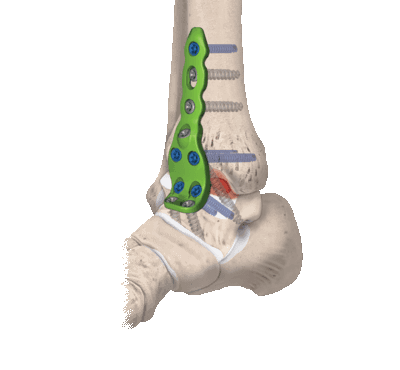

Рис. 2. Рентгенограммы пациента К. после операции: большеберцово-таранно-пяточный артродез с устранением всех видов деформации голеностопной области, фиксация проведена ретроградным блокируемым гвоздем Osteomed

Больному предложено хирургическое лечение, согласие пациента на хирургическое лечение получено. Выполнена операция: корригирующий большеберцово-таранно-пяточный артродез слева, фиксация ретроградным блокируемым гвоздем Osteomed, костная аутопластика (рис. 2).